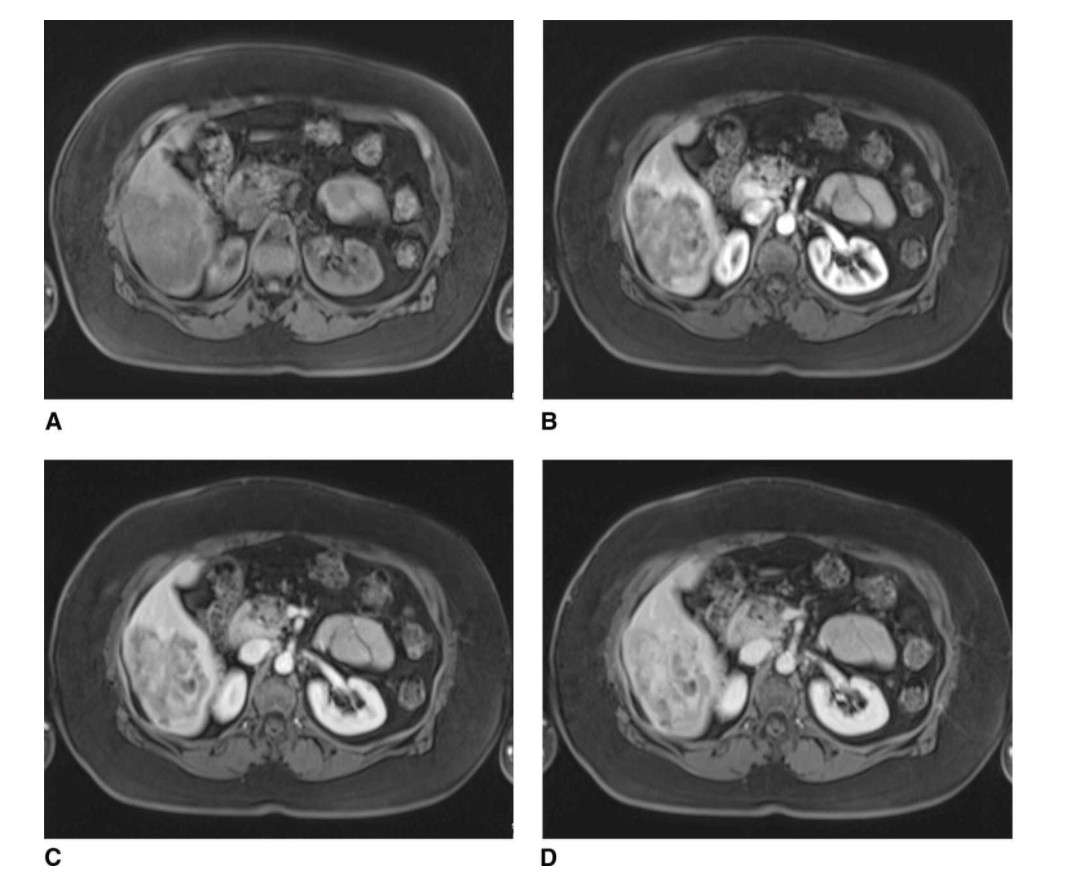

LIver lesion imaging characteristics

cholangiocarcinoma (characteristics)

delayed venous enhancement.

HCC imaging characteristics

arterial enhancement with venous washout